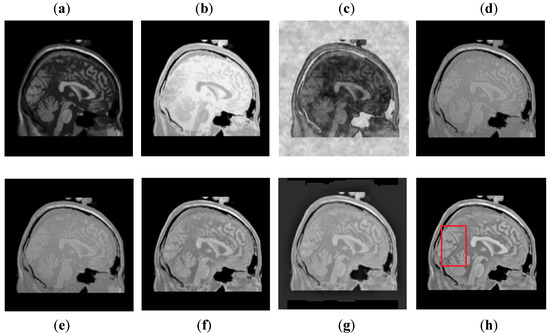

It can be observed in Figure 7 that images obtained by DCT have more noise and artifacts that distort the quality of a final image. The DWT method produces less noise than DCT, but the overall image is blurred, which affects the quality of the image. The NSST-SF-PCNN and CSR have better visual effects and produce better quality, but the image is still blurred, and some information is lost. The CNN method produces better results, and the image is more vivid and smooth than other existing methods, but its contrast and sharpness of the edges are still not up to the mark. It can be analyzed that the proposed method acquires better results than all mentioned fusion methods. The fused image has very negligible noise with better contrast. The edges are sharper with smoother boundaries. Hence, the final image has better visual effects with more salient information.

Figure 7. Data-1: (a) CT image, (b) MRI image, (c) DCT, (d) DWT, (e) NSST-SFT-PCNN, (f) CSR, (g) CNN, and (h) Proposed.